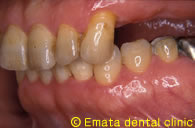

上顎の入れ歯があわない。自分の歯のように食べたい。

Before

After